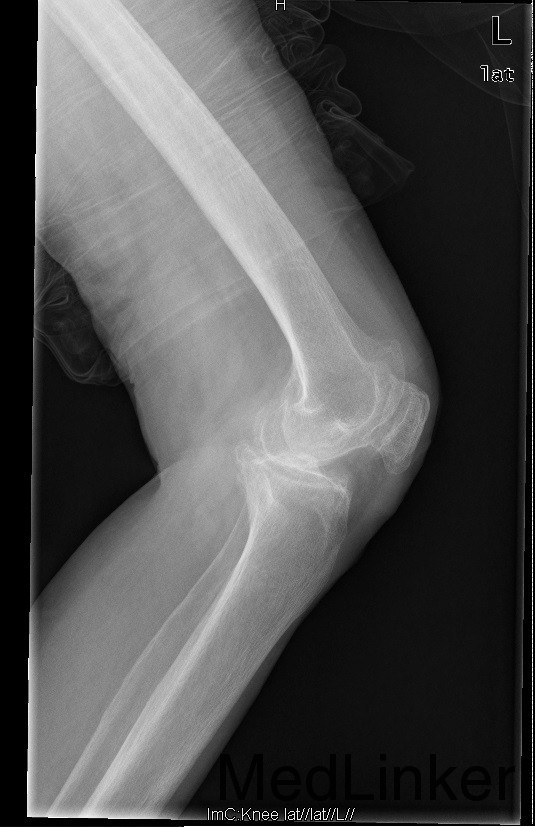

查体:跛行步态,左侧股内侧肌萎缩,左膝内侧关节间隙压痛,左膝髌股关节间隙压痛。左膝伸-45°,屈90°,左膝屈伸活动时髌骨下摩擦感 (+)。 辅助检查:左髌股关节内侧间室变窄,关节边缘骨赘增生,软骨下骨硬化

诊断:1、左膝骨关节炎伴屈曲畸形 2、左髌骨骨折骨愈合 治疗:积极行术前准备后于全麻下行左侧全膝关节置换术+软组织松解术,术后常规治疗。